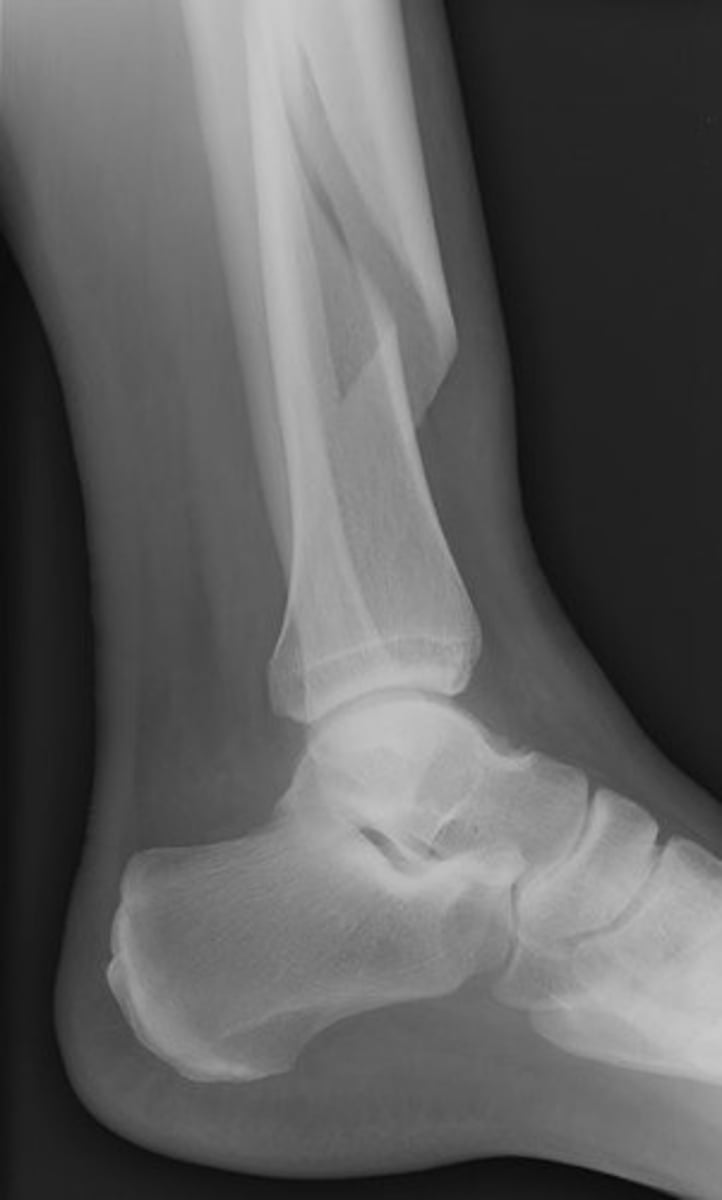

Fracture of the lateral malleolus, medial malleolus, and distal posterior tip of tibia

Trimalleolar fx

Complete fracture of distal fibula, frequently with fracture of medial malleolus

Pott's fx